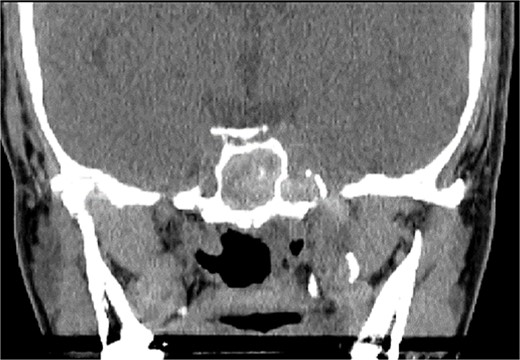

A 36 years-old man with no previous history of medical disease presented to the otolaryngology clinic with a chief complaint of headache that was associated with pressure feeling mainly in the occipital area. He also reported a post-nasal drip. The patient underwent a non-contrast paranasal sinus CT scan (Fig. 1) that demonstrated an isolated sphenoid sinus homogenous opacification, most likely representing sphenoid fungal ball. A decision was made to proceed with endoscopic sphenoidotomy (Fig. 2) to clean and remove the debris, which confirmed the diagnosis of sphenoid sinus fungal ball.

Coronal (A) and axial (B) images of a nonenhanced CT scan of the paranasal sinuses showing left sphenoid sinus complete homogenous opacification.